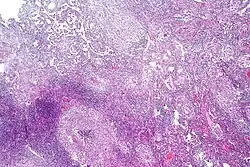

Chest X-ray and CT

Tuberculosis creates cavities visible in x-rays like this one in the patient's right upper lobe.

In active pulmonary TB, infiltrates or consolidations and/or cavities are often seen in the upper lungs with or without mediastinal or hilar lymphadenopathy or pleural effusions ( tuberculous pleurisy). However, lesions may appear anywhere in the lungs. In disseminated TB a pattern of many tiny nodules throughout the lung fields is common - the so-called miliary TB. In HIV and other immunosuppressed persons, any abnormality may indicate TB or the chest X-ray may even appear entirely normal.

Abnormalities on chest radiographs may be suggestive of, but are not necessarily diagnostic of, TB. However, chest radiographs may be used to rule out the possibility of pulmonary TB in a person who has a positive reaction to the tuberculin skin test and no symptoms of the disease.

Cavitation or consolidation of the apexes of the upper lobes of the lung or the tree-in-bud sign[15] may be visible on an affected patient's chest X-ray.[1] The tree-in-bud sign may appear on the chest CTs of some patients affected by tuberculosis, but it is not specific to tuberculosis.[15]